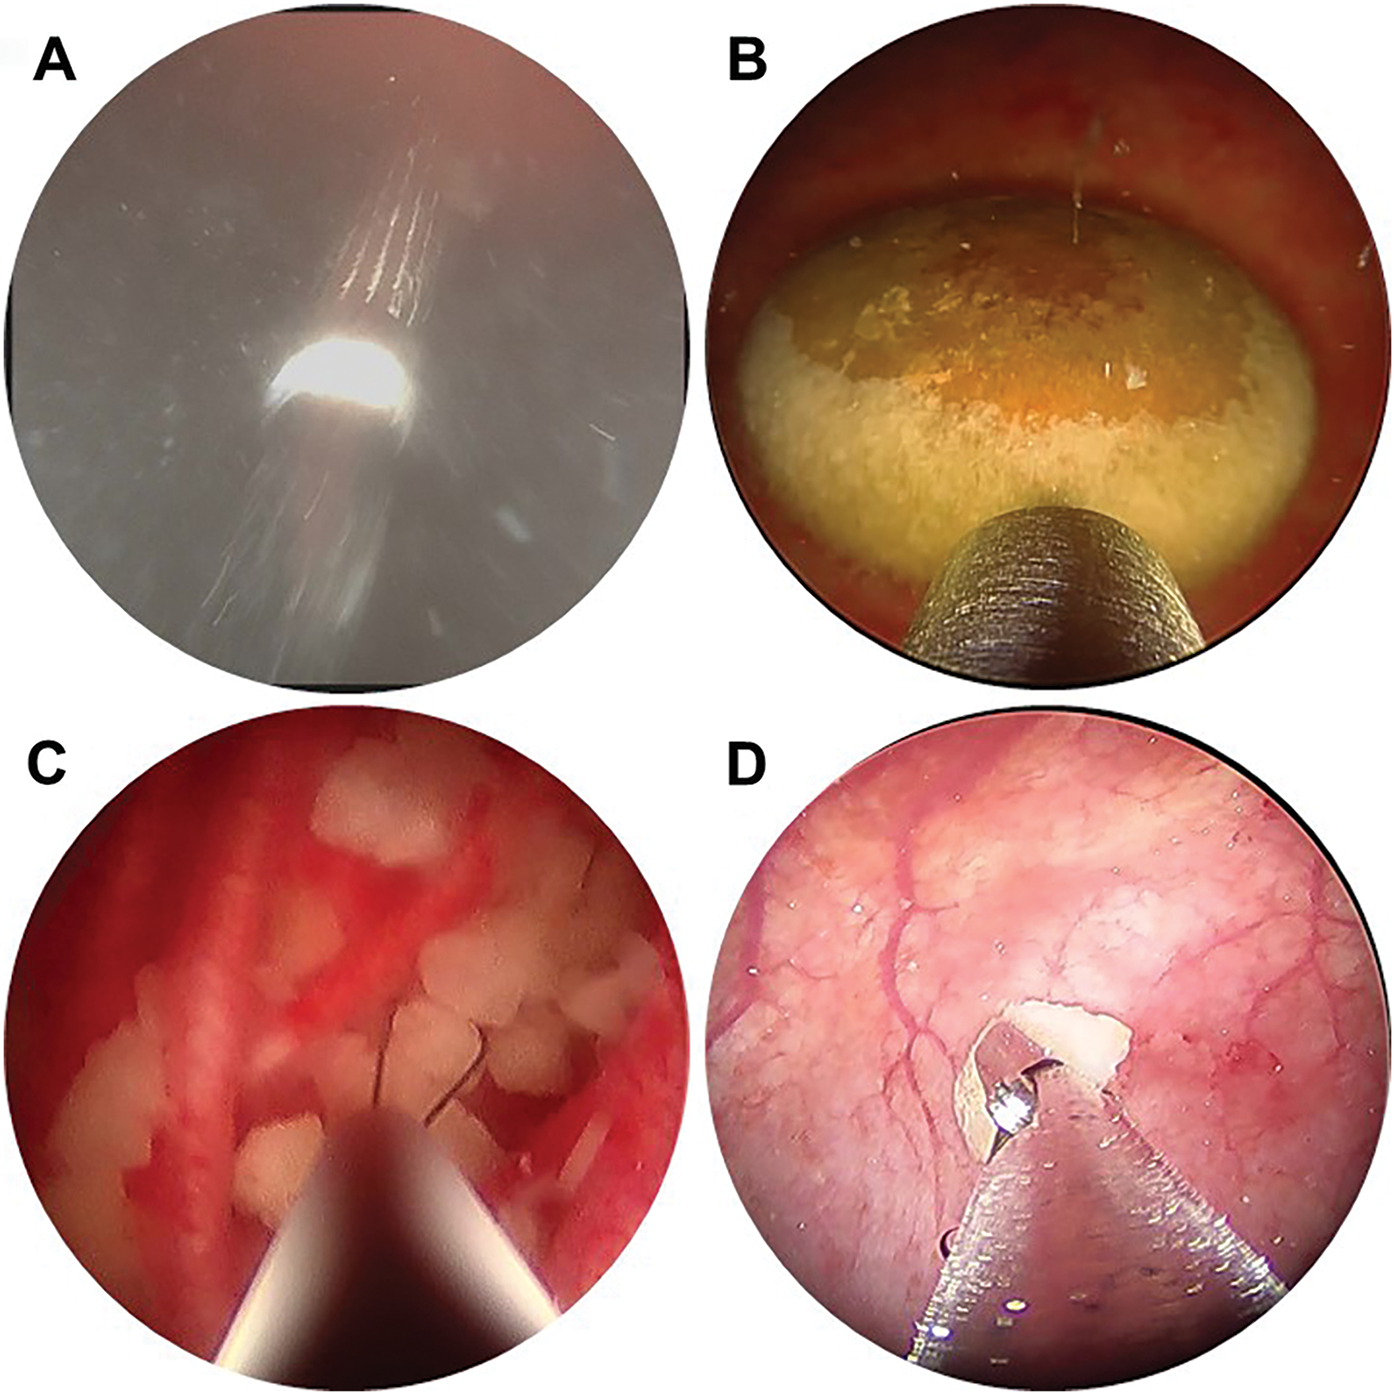

The technique for initial access mirrors percutaneous renal access. Scout fluoroscopy can confirm the stone position (Figure 1A). We perform the initial puncture using a percutaneous access needle (Boston Scientific NaviGuide™ Percutaneous Access Needle, 18 gauge). A bull’s eye technique facilitates a midline suprapubic puncture directly over the stone (Figure 1B). Successful bladder entry should yield urine return through the hollow needle. Two guidewires are passed and curled in the bladder. The safety wire is secured to the drape. If the access is performed under vision, needle entry and wire passage may be confirmed directly (Figure 2A). In patients with a pre-existing suprapubic tube (SPT), a guidewire may be directed through or alongside the catheter to obtain access. Performing a cystogram through the SPT may help confirm the wire position.

Figure 2: Intraoperative endoscopy demonstrating (A) percutaneous needle puncture under direct vision, (B) bladder stone with Swiss LithoClast® Trilogy lithotripter probe, (C) basket extraction of stone fragments, (D) extraction of stone fragments using grasping forceps

Various devices can be used for stone fragmentation and evacuation. We generally prefer the Swiss LithoClast® Trilogy, as the combination of ballistic and ultrasound energy and suction evacuation facilitates highly efficient stone removal (Figure 2B). Smaller stones or residual fragments may be extracted using a basket such as the Cook Medical Perc NCircle® basket (Figure 2C) or grasping forceps (Figure 2D). When patient anatomy allows, advancing a flexible cystoscope or ureteroscope per urethra or catheterizable channel helps locate residual fragments and relocate them for treatment via the percutaneous tract. Stone fragments may be collected for composition analysis. In patients with recurrent or elevated infection risk, we obtain a bacterial and/or fungal culture of stone material.